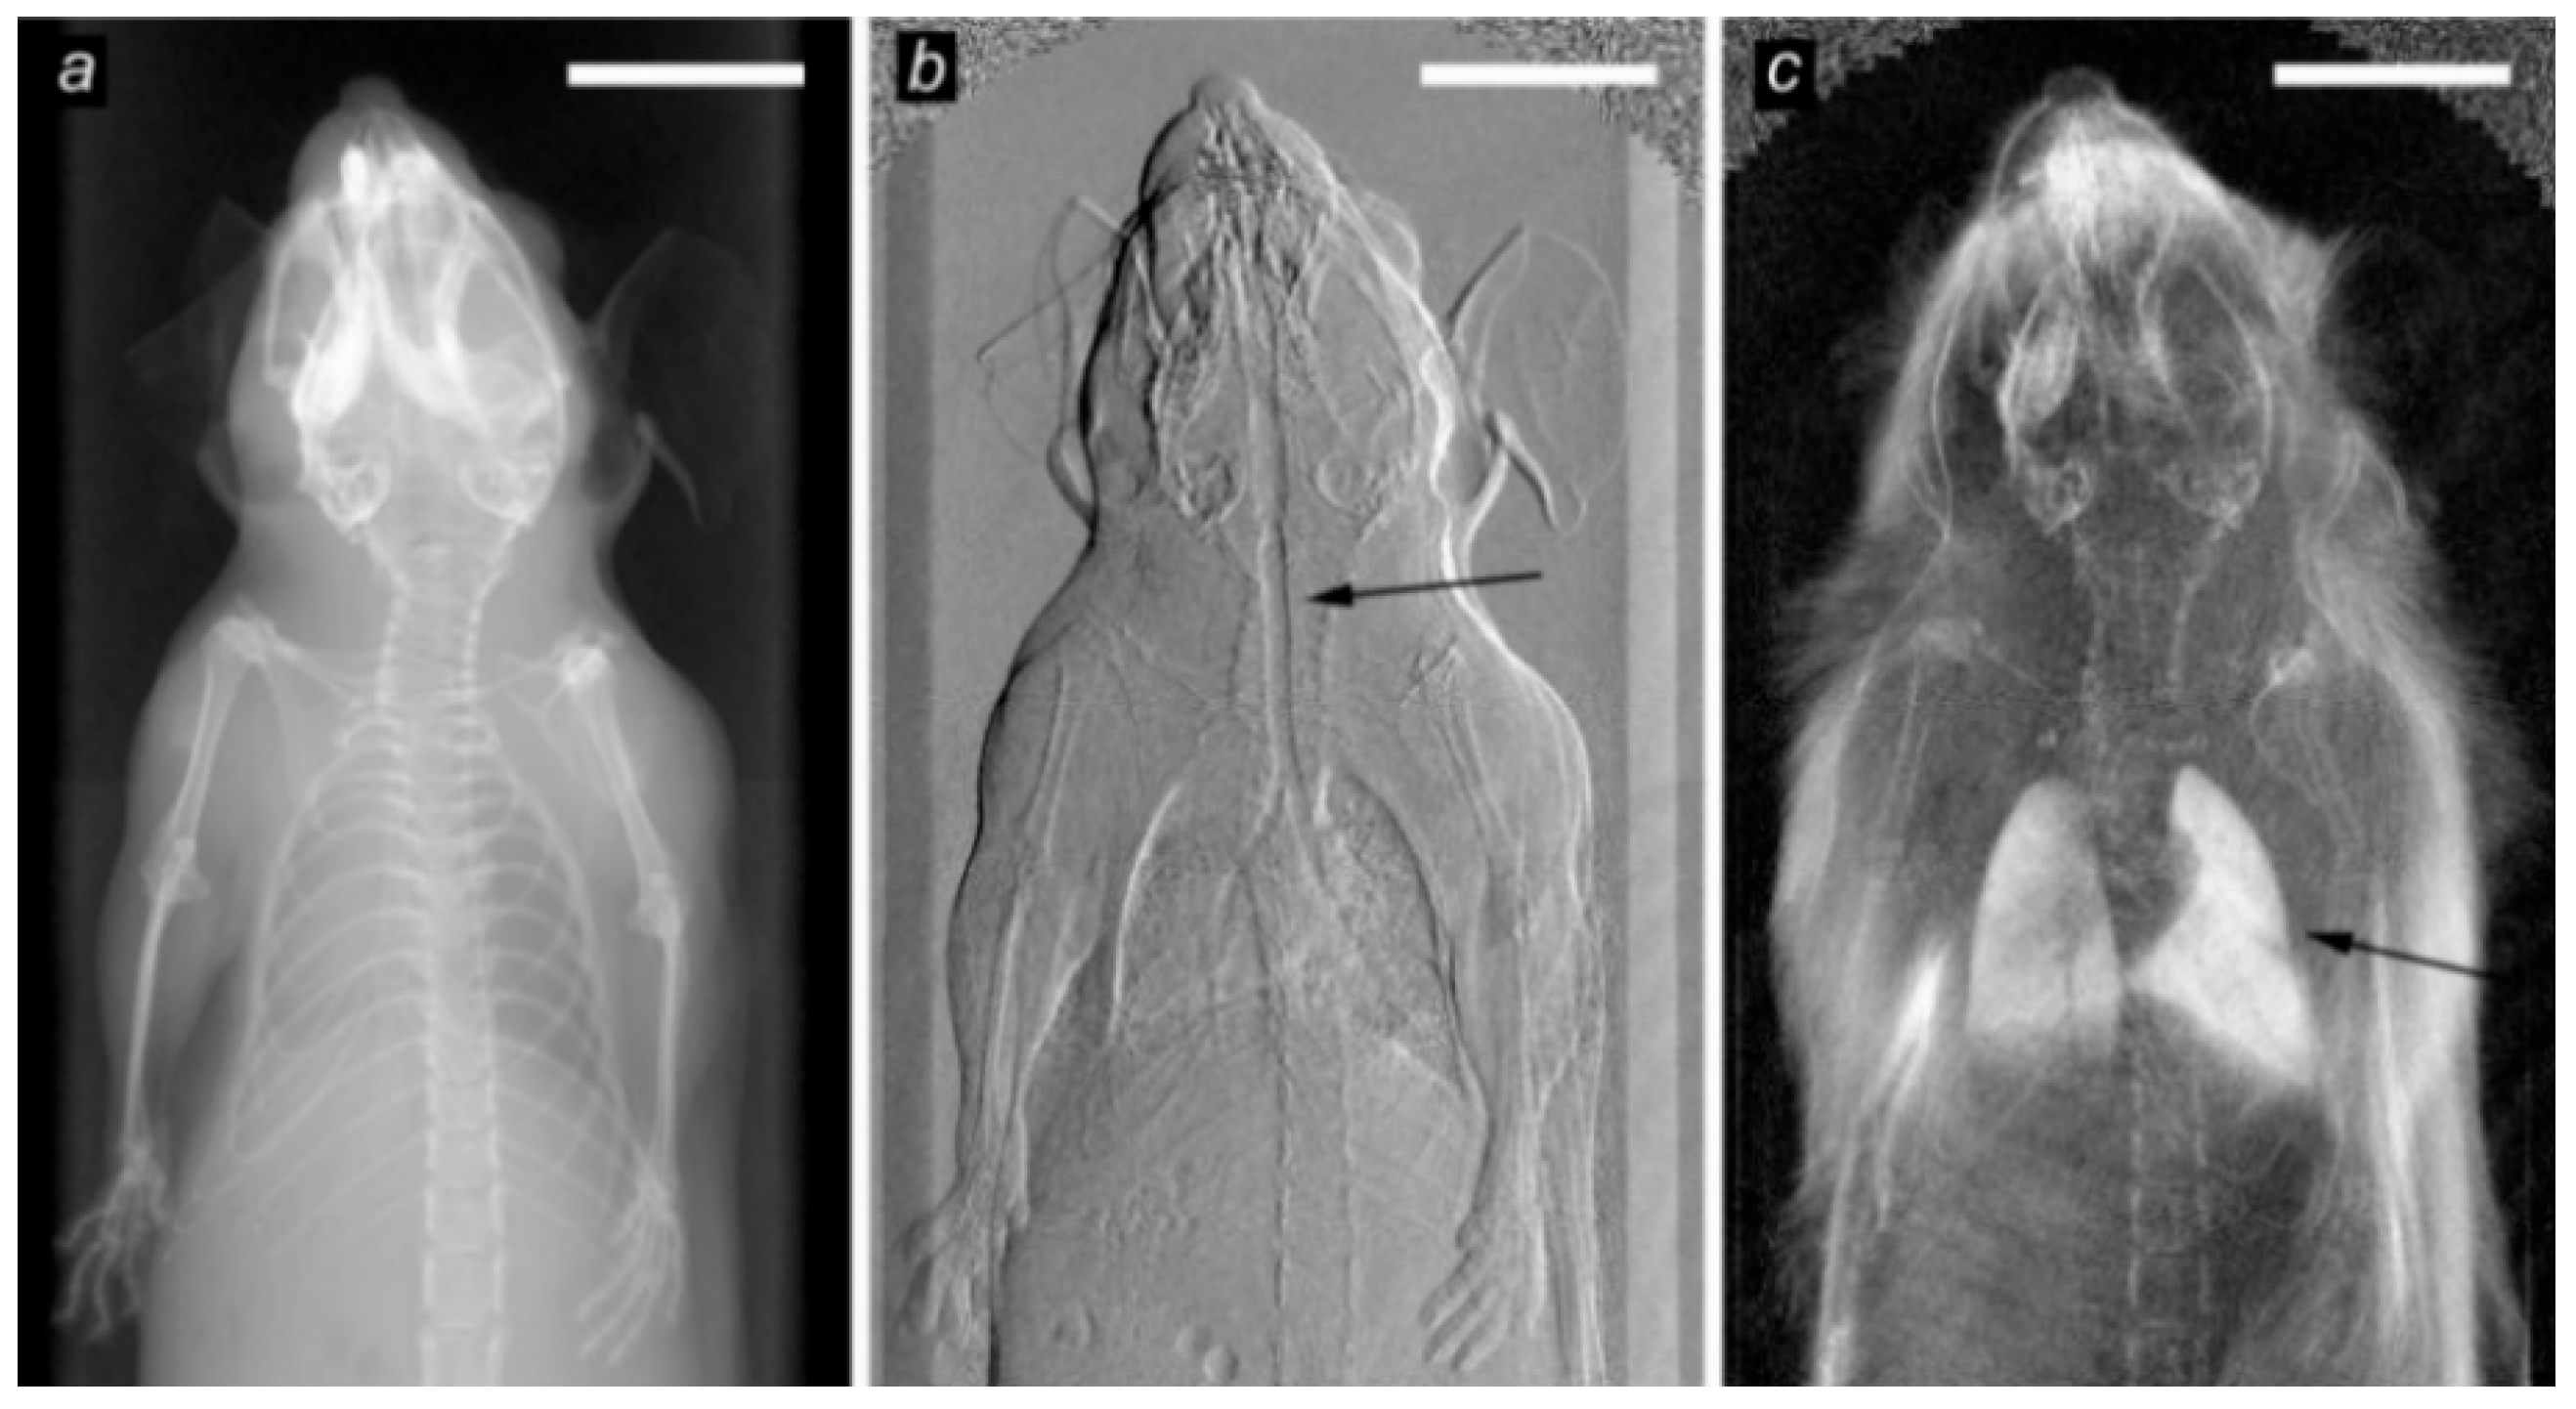

- Scherer, K.; Yaroshenko, A.; Bölükbas, D.A.; Gromann, L.B.; Hellbach, K.; Meinel, F.G.; Braunagel, M.; Bergens, J.V.; Eickelberg, O.; Reiser, M.F.; et al. X-ray dark-field radiography in-vivo diagnosis of lung cancer in mice. Sci. Rep. 2017, 7, 1–8. [Google Scholar] [CrossRef]